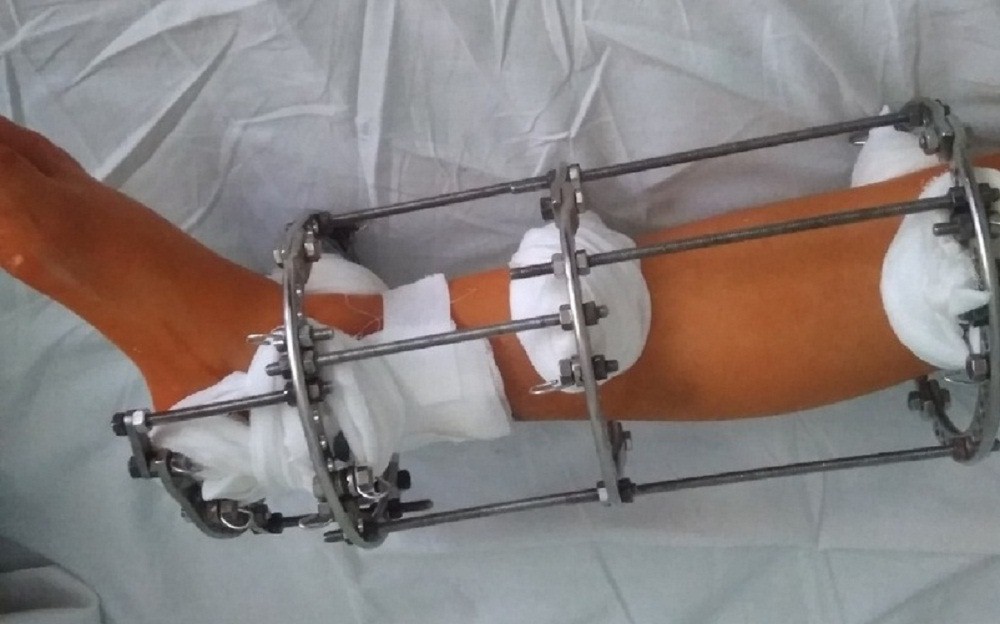

Аппарат Илизарова: принцип работы и применение